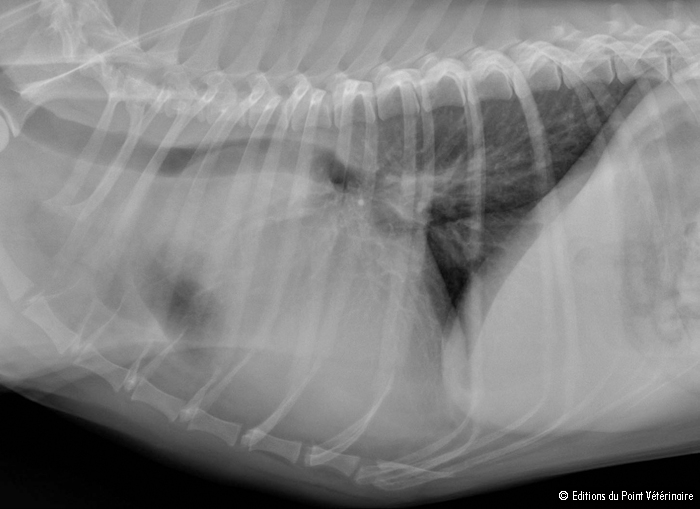

March 2022:

Cavalier with difficulty in breathing found to have a cancerous

tumor in the heart.

In

a

March 2022 article, UK researchers (Alex Shirlow, Kieran Borgeat,

Nicolette Hayward, Emma Scurrell, Jessie Rose Payne [right]) a

cavalier King Charles spaniel displaying dyspnea (shortness of breath)

and tachypnea (rapid breathing) and a mild mitral valve murmur, was

suspected of the onset of congestive heart failure due to mitral valve

disease (MVD). However, they found that the dog's heart rhythm was

regular and that the size of the heart and the pulmonary vessels were

within normal limits. Echocardiography detected a mass which was

limiting the inflow of blood to the left side of the heart. Also, the

dog's right eye showed blood collected between the cornea and the iris,

and secondary glaucoma. A tumor was suspected within the heart, and the

dog was euthanized due to a grave prognosis. Post-mortem examination

revealed a metastatic osteosarcoma tumor in the left atrium and

pulmonary vein, metastatic osteosarcoma in the myocardium, lungs, the

uveal tract of the right eye, and both adrenal glands. Whitney grade II

myxomatous changes were noted on the mitral and tricuspid valve

leaflets. The investigators cautioned that although cavaliers with

dyspnea often raise suspicion of MVD, other more unusual causes of

dyspnea should also be considered in the absence of classic clinical MVD

findings.